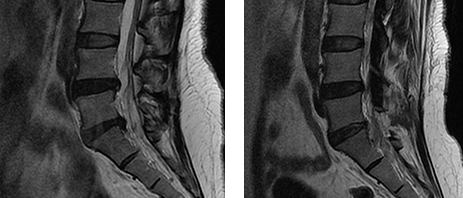

자기공명영상 검사 (MRI)

가장 정확한 검사법으로 추간판 탈출 정도나 척추의 손상 및 신경의 압박 정도, 인대 근육 등의 조직 손상까지 확인이 가능합니다.